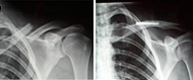

Las luxaciones acromioclaviculares son producidas por traumatismos en el hombro y producen la separación entre la clavícula y el acromion. La fuerza deformante puede llegar al hombro de forma directa (impacto sobre el hombro) o de forma indirecta tras caída sobre la mano con la extremidad extendida y transmisión del impacto al hombro.Son típicas de la segunda y tercera década de la vida afectando casi siempre al sexo masculino por su mayor predisposición a los deportes de velocidad (motociclismo, automovilismo, ciclismo, esquí) y de contacto (karate, judo, tae-kwon-do).

En función de la separación entre los huesos que forman la articulación (acromion y clavícula) el tratamiento puede ser conservador o quirúrgico.

Cuando la separación es grande y la posibilidad de restauración por métodos conservadores es imposible proponemos una rápida y mínima intervención para la reparación articular definitiva